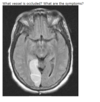

infarct in MCA territory leading to all loss of fibers losing vision on opposite side